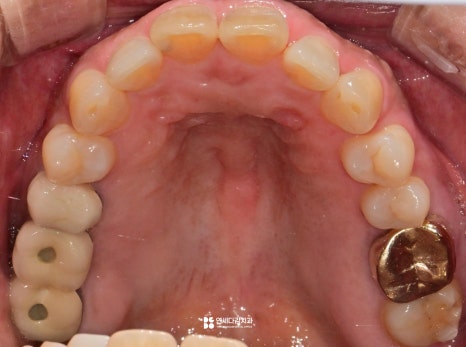

이렇게 눈으로 살펴봤을 때는

특별한 이상은 없는 것처럼 보이지만,

실제로는 통증을 느끼는 경우가 있습니다.

이는 구강 안에 육안으로 확인하기 어려운

사각지대가 존재하기 때문입니다.

이 사각지대 중 하나가 인접면입니다.

치아의 옆면은 음식이 자주 끼는 곳이지만,

이물질을 제거하기 어렵고 확인도 어렵기 때문에

우식이 자주 발생하는 부위입니다.